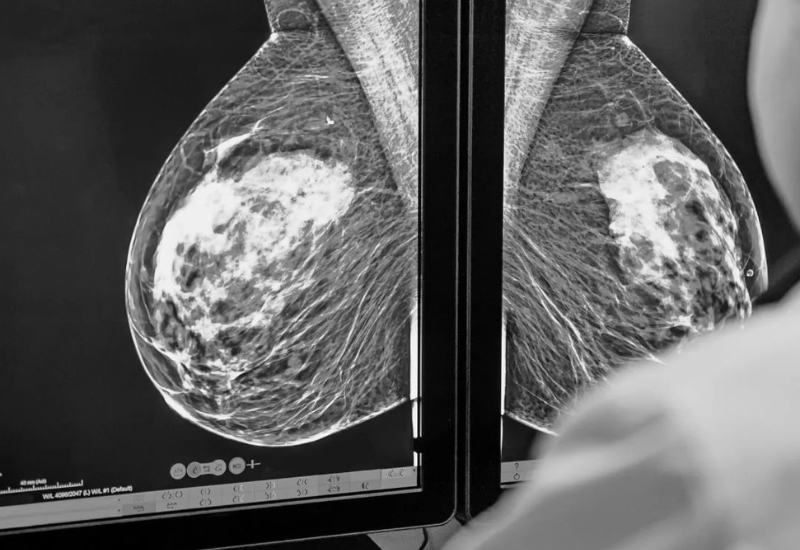

Khi hoạt động, tia X được phát ra từ ống phát tia, xuyên qua cơ thể người bệnh và được thu lại ở đầu đối diện. Các mô đặc như xương hấp thụ nhiều tia X hơn nên hiện lên màu trắng, trong khi mô mềm hấp thụ ít hơn, hiển thị màu xám hoặc đen. Dựa trên hình ảnh đó, bác sĩ có thể đánh giá cấu trúc xương, phát hiện gãy xương, tổn thương phổi, khối u, dị vật…

- Mang lại hình ảnh giải phẫu sắc nét, cho phép bác sĩ phát hiện tổn thương vi thể mà mắt thường khó thấy;